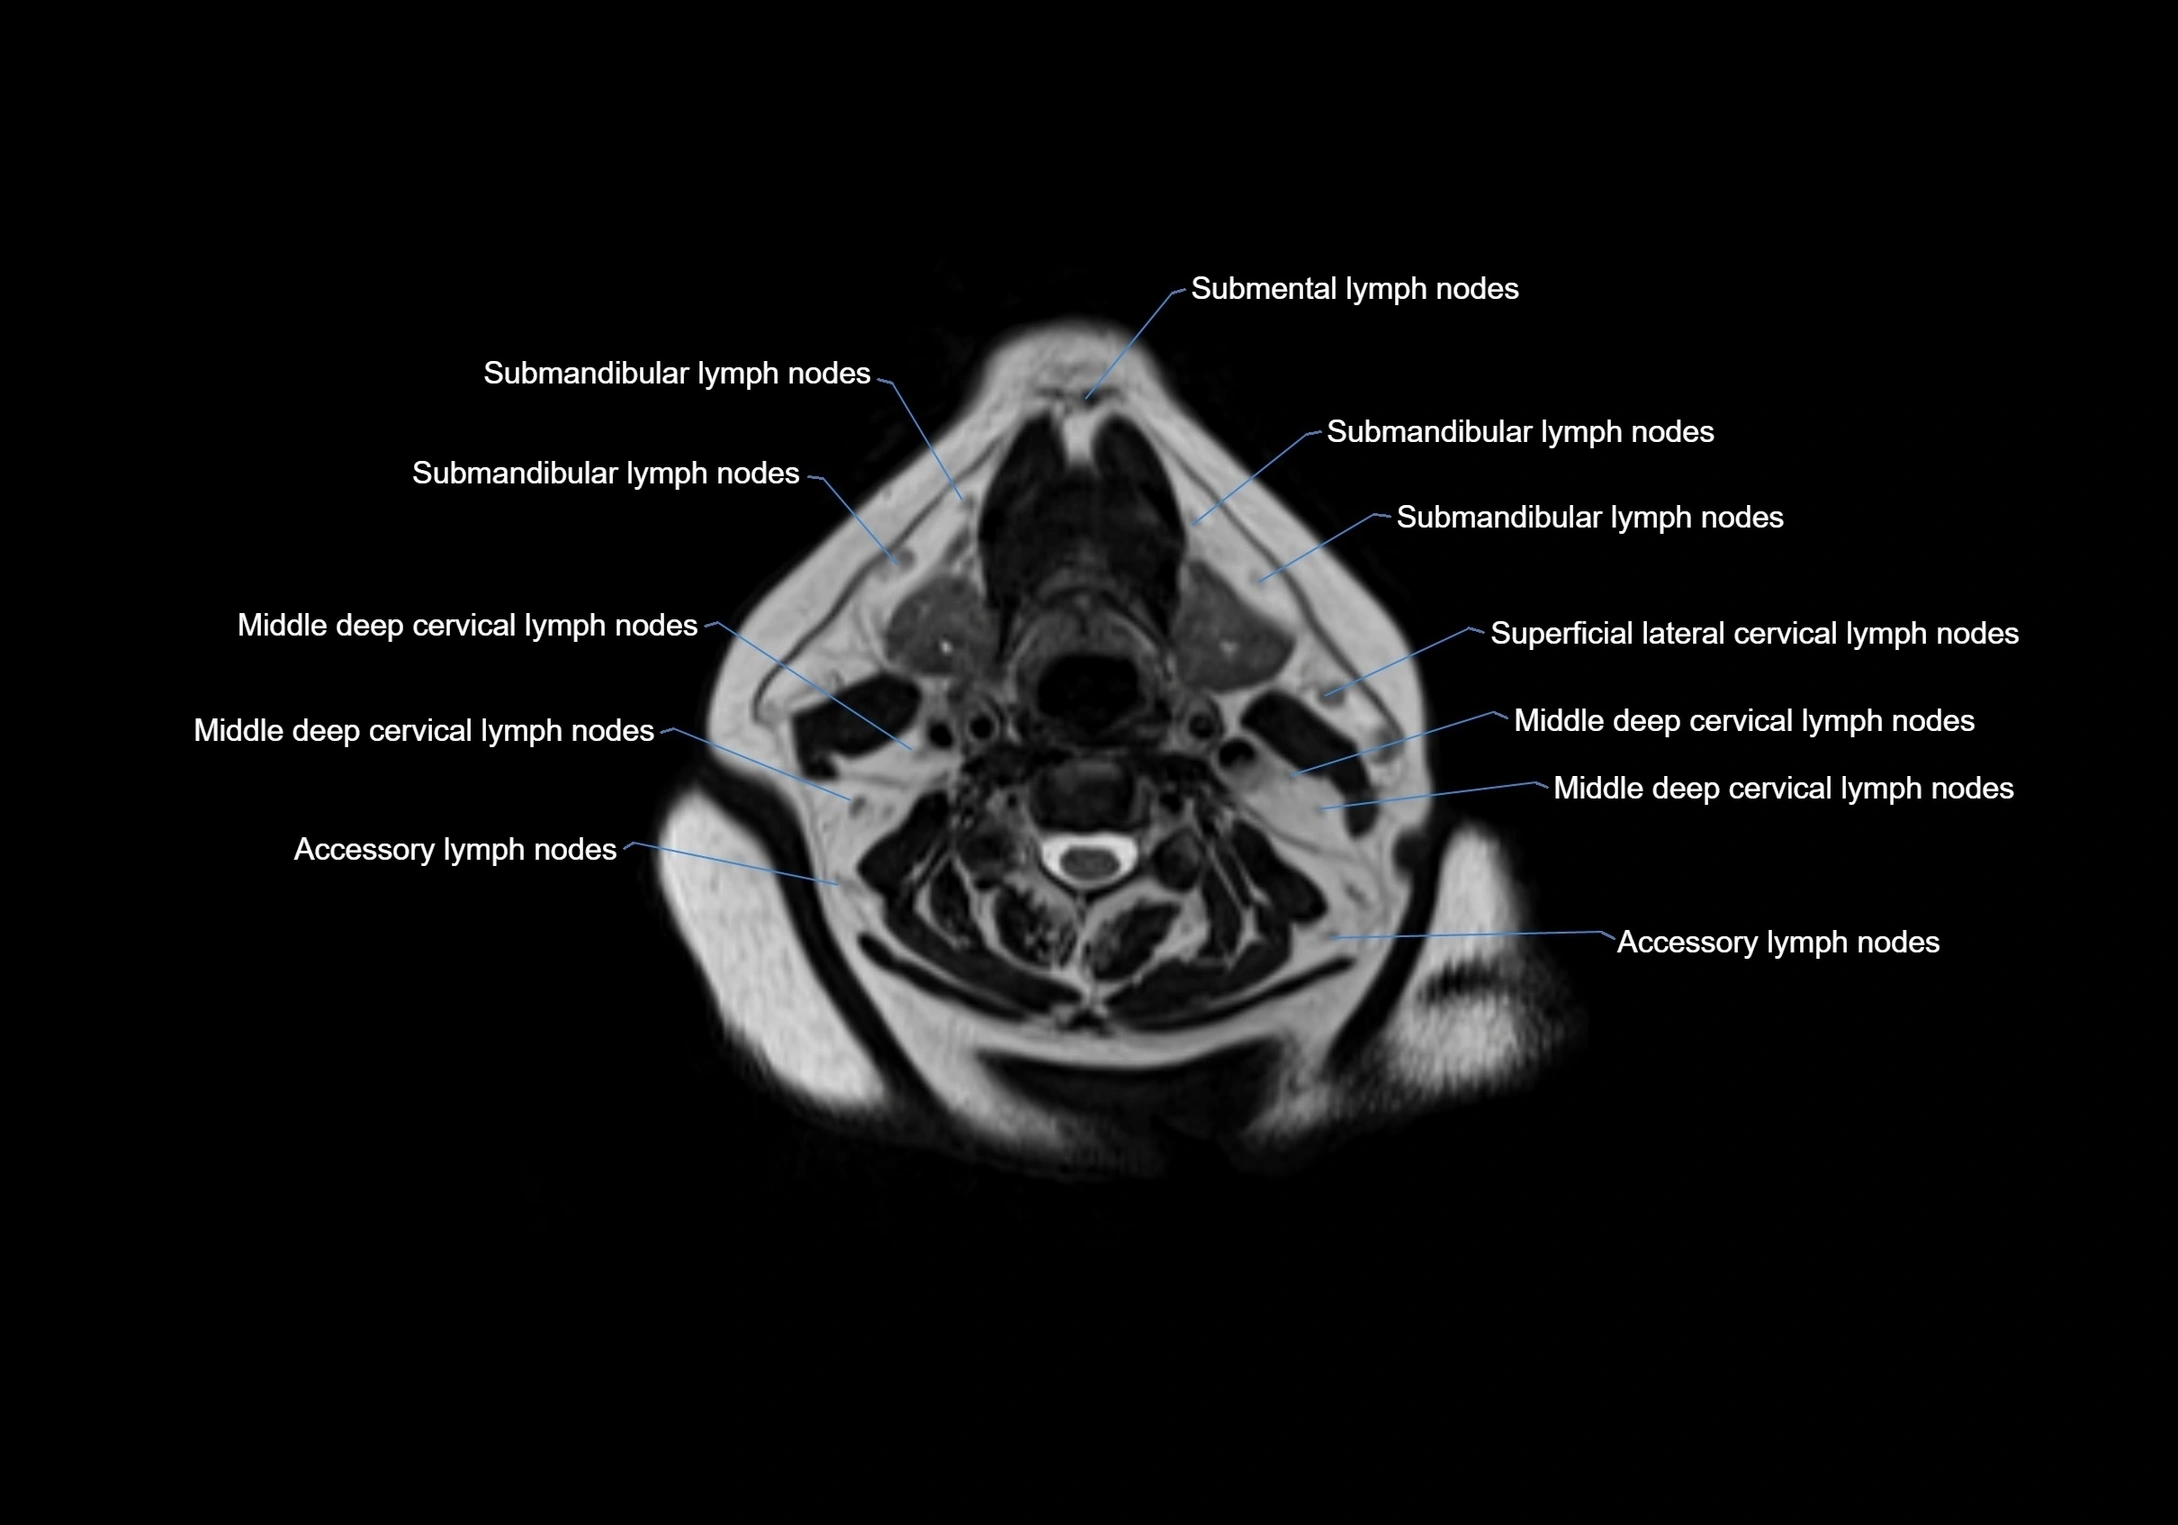

Accessory lymph nodes

Accessory lymph nodes are small, secondary lymph nodes located along the main facial and cervical lymphatic chains, often adjacent to primary lymph nodes, such as preauricular, submandibular, or occipital nodes. They are typically less than 5 mm in diameter, embedded within subcutaneous fat or connective tissue, and may be variable in number and location. These nodes provide additional filtration and immune surveillance for lymph collected from the face, scalp, and neck regions. Accessory lymph nodes are usually non-palpable in healthy individuals but may enlarge in response to infection, inflammation, or metastasis, making them clinically significant.

Location

• Found along primary lymph node chains, including preauricular, submandibular, parotid, and occipital regions

• Embedded in subcutaneous fat or superficial fascia, often lateral or posterior to primary nodes

• Variable in number; may occur unilaterally or bilaterally, depending on individual anatomy

MRI images

image